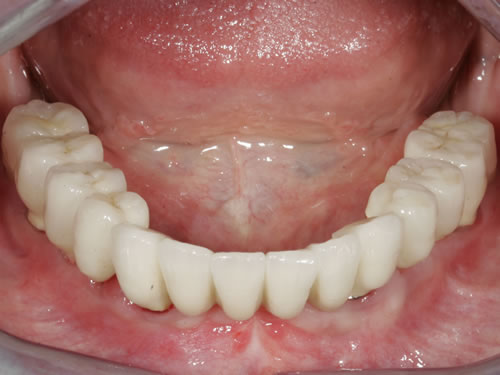

In bestimmten Situationen kann auch die Versorgung durch einen festsitzenden Zahnersatz, also durch eine Brücke, sinnvoll sein (Abb. 3.13, 3.14). Hier müssen allerdings relativ viele Pfeiler eingepflanzt werden. Mit der Anfertigung einer Brücke entstehen gewisse Probleme bei der notwendigen Mundhygiene und natürlich sehr hohe Kosten. Daher wird sie nur in besonderen Fällen in Frage kommen.

Abb. 3.13: Zahnloser Unterkiefer mit 8 Implantaten festsitzend versorgt.

Abb. 3.14: Ansicht der einzementierten Brücke.

Für den zahnlosen Ober- und Unterkiefer werden dies häufiger Stegkonstruktionen oder Teleskopversorgungen sein (Abb. 8.8 bis 8.16).

Auch eine festsitzende zementierte oder verschraubte Brücke ist möglich (Abb. 8.17 bis 8.19). Hierbei muss eine günstige Lachlinie vorliegen und der Kieferschwund sollte noch nicht zu weit fortgeschritten sein. Die Zähne würden sonst sehr lang wirken, da die Zahnpositionen in die ehemalige Position der Zähne zurückgebracht werden muss. Langes Prothesentragen und entsprechender Knochenverlust erschweren besonders im Oberkiefer festsitzenden Zahnersatz. Sehr exakte Voruntersuchungen und präzise Implantatpositionen mit entsprechenden Knochenaufbaumaßnahmen sind häufig notwendig, um den Patienten diesen Wunsch zu erfüllen.